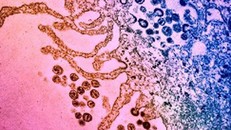

(Ngày Nay) - Tình trạng kháng kháng sinh (AMR) đang gia tăng nhanh chóng và trở thành một vấn đề y tế toàn cầu nghiêm trọng. Theo ước tính, AMR đã gây ra 4,95 triệu ca tử vong tính đến năm 2019, và con số này có thể tăng lên 10 triệu ca vào năm 2050 nếu không có biện pháp can thiệp.

(Ngày Nay) - Tổ chức Y tế Thế giới (WHO) gọi tình trạng kháng thuốc kháng sinh (AMR) là “đại dịch thầm lặng", khi mỗi năm ước tính có khoảng 1,3 triệu người tử vong trực tiếp do mầm bệnh kháng thuốc.